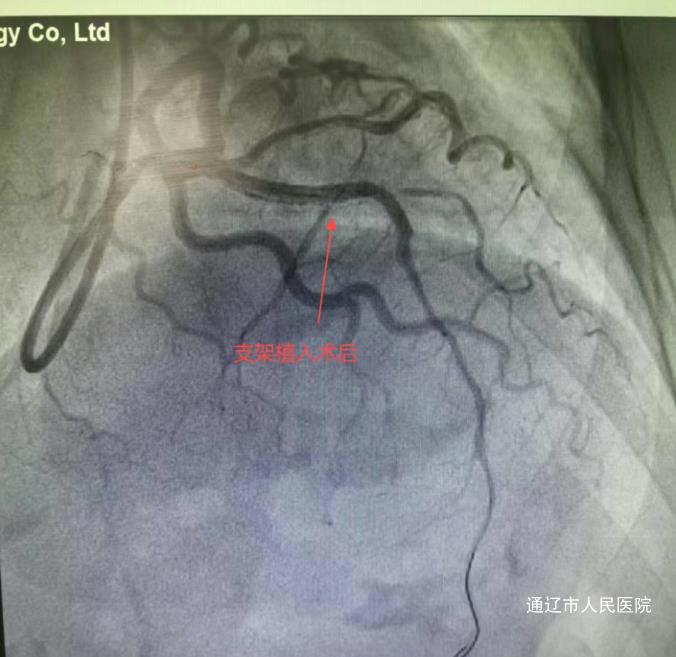

次日,心血管内三科团队采用经桡动脉微创介入技术,在血管内超声(IVUS)引导下为患者手术。术中造影显示其冠状动脉前降支狭窄达99%伴血栓形成,血管动脉硬化较重伴迂曲钙化。团队运用多种先进技术,历时65分钟成功植入两枚药物支架。术后李奶奶胸痛缓解,次日可下床活动,4月16日康复出院。患者及家属对治疗效果非常满意,通过快手平台发布感谢视频,真实记录就医全过程,视频获得近10万点播量,家属在视频中感谢医护人员创造奇迹并感谢医护人员的精心治疗和照顾。